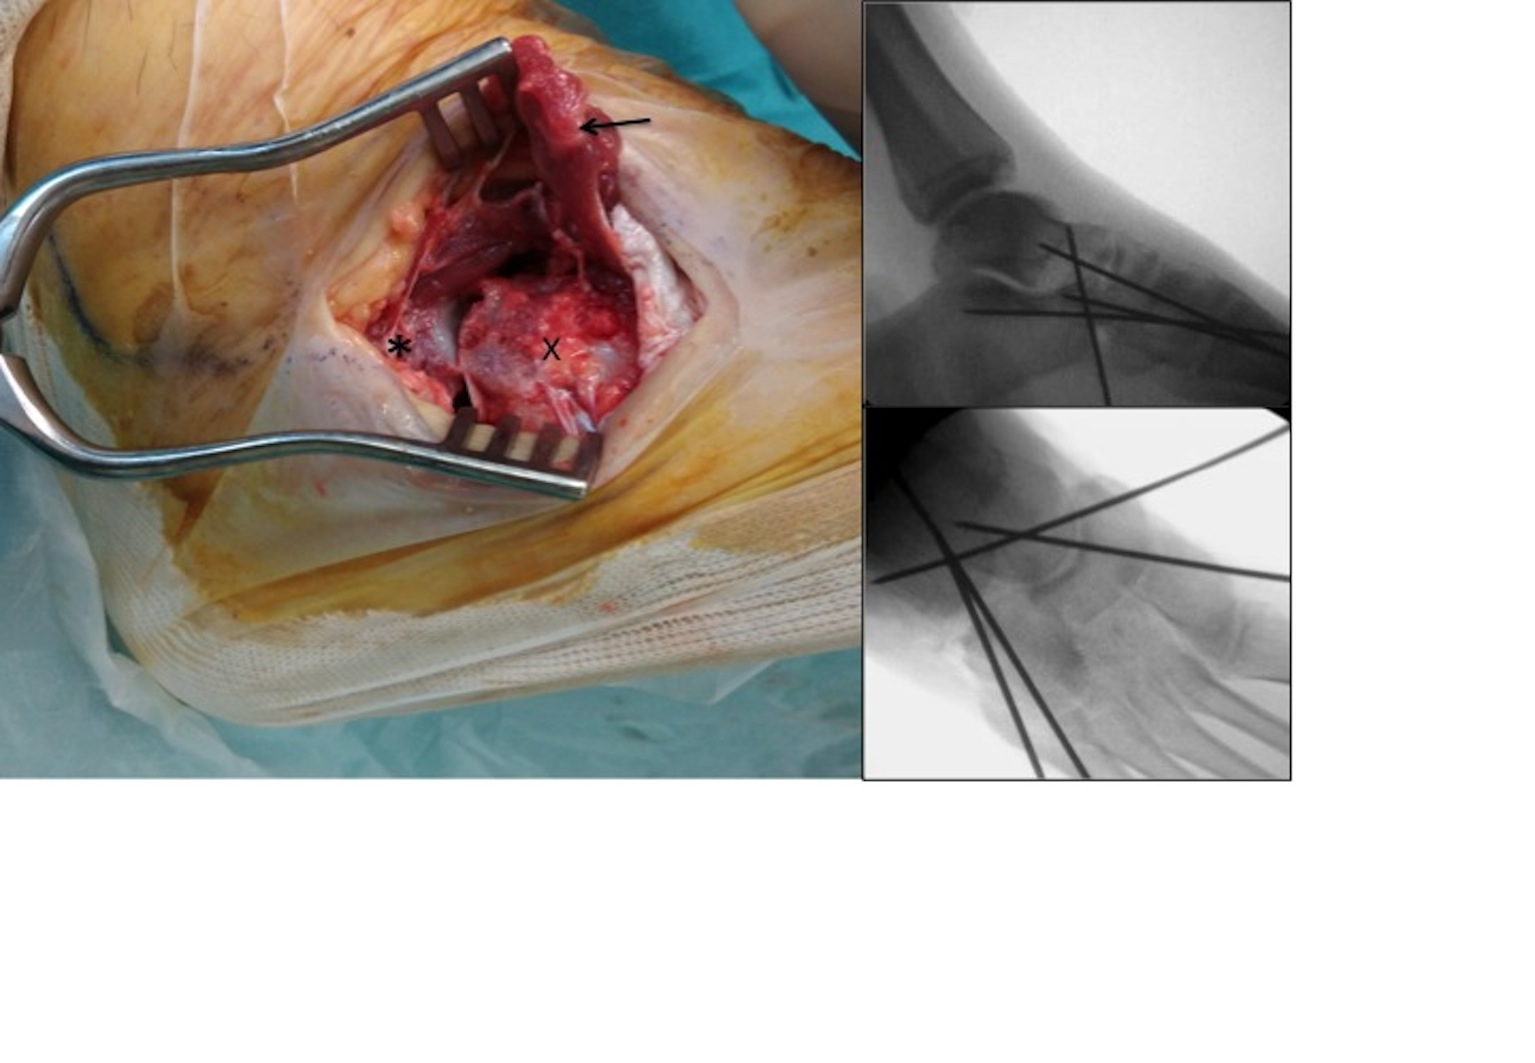

Se presenta el caso de una luxación mediotarsiana en una mujer de 19 años de edad que fue diagnosticada a las ocho semanas de evolución. Se realizó una reducción abierta a través de un doble abordaje (medial y lateral) y una estabilización de las articulaciones con agujas de Kirschner. Al año de la intervención, no se observó pérdida de reducción y la paciente no presentó dolor, pero si limitaciones funcionales para realizar deportes de carrera.